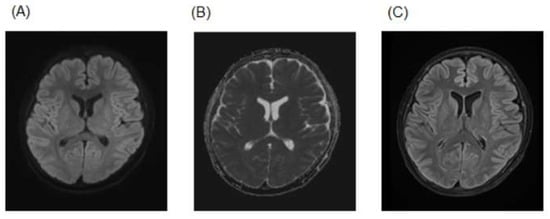

2. Case Presentation

| This Case | MERS | 18/m | Orthostatic hypotension | Confusion | Yes | No | No | 128.9 mEq/L | Normal | High | Low | High | Follow-up MRI (11 days): complete regression of the corpus callosum lesion | No | Remdesivir | Recovery |